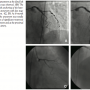

Patient #2. A 62-year-old female with history of hypertension, diabetes mellitus, systemic lupus erythematosous and recent non-ST elevation MI presented with exertional angina that had worsened over the course of the preceding month and ischemia at the anterolateral wall in the scintigraphy. Coronary angiography revealed aneurysm at the ostium and critical post-aneurysmatic stenosis at the proximal part of the first diagonal branch. There were no additional hemodynamically significant stenoses in the coronary tree (Figures 2A and 2B). A PCI at the bifurcation of the first diagonal branch with wire protection at the LAD was performed. After predilatation with a 2 x 10 mm Sprinter balloon (Medtronic) at 12–16 atm, careful anchoring of a 2.5 x 14 mm Driver stent at 16 atm to the distal non-diseased segment was performed. The final angiographic result was excellent, with dye stagnating inside the aneurysm and the patient was discharged uneventfully the following day (Figure 2C). At 6-month angiographic follow-up, significant in-stent restenosis and complete abolition of the aneurysm was observed (Figure 2D). The restenostic lesion was treated with placement of a 2.5 x 18 mm Cypher stent at 16 atm. After 12 months, the patient was asymptomatic and the myocardial scintigraphy showed no ischemia at the anterolateral wall.